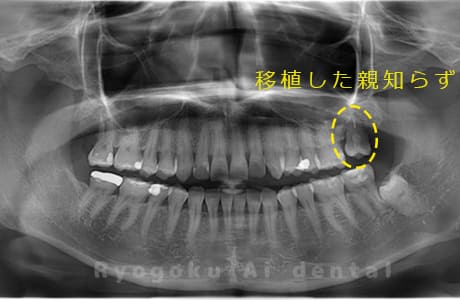

Case27

-

重度カリエス

歯牙移植咬合面術前 -

移植する親知らず

歯牙移植術直後咬合面

歯牙移植術後咬合面

歯牙移植術前側面

歯牙移植術中側面

歯牙移植術後側面

- 原因

- 重度カリエス

- 治療内容

- 自家歯牙移植、部分矯正

- 治療費用

- 220,000円(移植費用)

110,000円(部分矯正費用)

虫歯が大きく、保存不可能となった歯を上の親知らずと交換する自家歯牙移植を行いました。移植歯が小ぶりであったため、部分矯正を行い問題なく噛み合い、経過良好です。